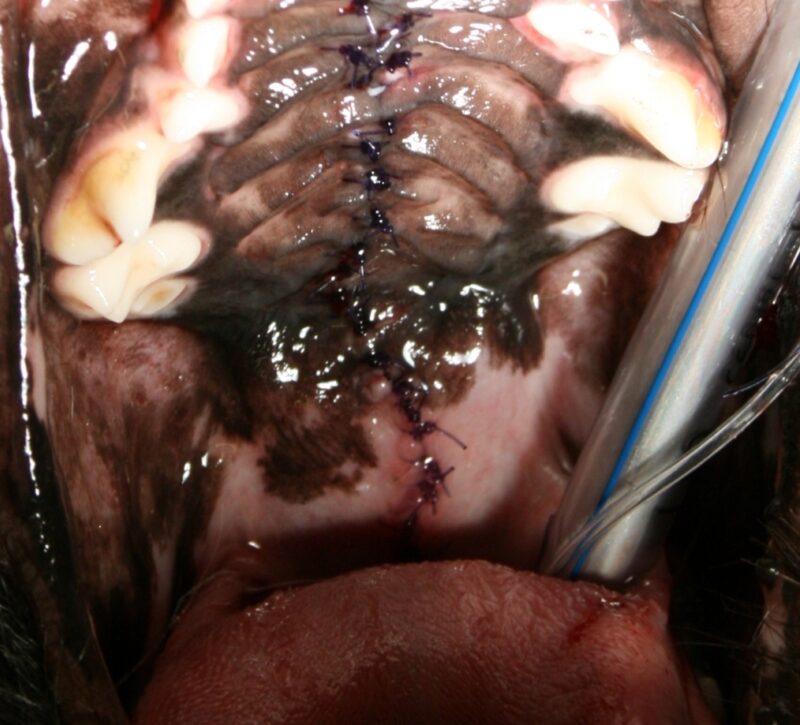

Nach Besprechung der Befunde mit der Besitzerin wurde die Gaumenspalte operativ in der gleichen Narkosesitzung verschlossen. Zuerst wurde die Gaumen-Schleimhaut im Bereich der Gaumenspalte sorgfältig abpräpariert, damit keine Epithelreste eine Wundheilung verhindern können. Bei der Blutstillung wurde auf HF-chirurgische Instrumente verzichtet, um die Blutgefäßversorgung und –integrität nicht negativ zu Beeinflussen. Nachdem die knöchernen Defekte im mittleren Bereich der Gaumenspalte nur sehr dezent waren und genug Schleimhaut zur Verfügung stand konnte auf Maßnahmen zur Mobilisierung weiterer Schleimhaut verzichtet werden. Im rostralen Bereich caudal der Papilla Incisivi mussten Entlastungsschnitte nahe des Margo alveolaris angelegt werden. Dies war notwendig, um die Gingiva des harten Gaumens zu mobilisieren und um einen spannungsfreien Wundverschluss gewährleisten zu können. Im Bereich des weichen Gaumens wurden Inzisionen angelegt und das Gaumensegel neu konstruiert. Die Naht erfolgte jeweils zweischichtig Stoß auf Stoß mit Monoplus 4/0 in Form von Einzelheften.